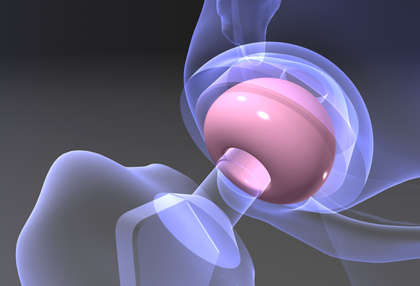

paracam arbeitet mit Industrieunternehmen, Museen, Kliniken, wissenschaftlichen Instituten und Fernsehsendern zusammen. Das Steinbeis-Transferzentrum ist darauf spezialisiert, technische und wissenschaftliche Daten und Phänomene mit den Mitteln moderner Medien-Tools zu visualisieren. Dabei sind in den vergangenen 30 Jahren zahlreiche und zum Teil preisgekrönte Filme, 3D-Animationen und interaktive Anwendungen entstanden.